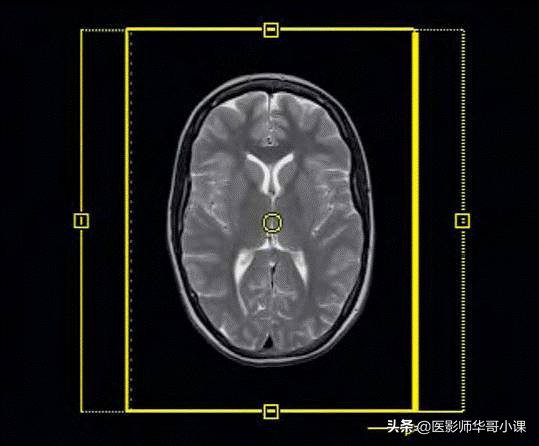

MRI 中的百慕大三角:相对信噪比(rSNR),扫描时间(Scan time)和分辨率(Resolution)

Syngo MR软件会自动计算在改变相关序列参数后,相对于之前的序列,图像信噪比所发生的改变。如果一个序列本身就具备足够的信噪比,即使改变序列参数后,相对信噪比变成0.1,仍有可能获得比较好的图像质量。但是假如我们不断的压缩扫描时间,空间分辨率达到一定程度后,图像噪声已经开始变明显增多。这时如果继续调整参数后,即使相对信噪比降为0.9,图像质量可能仍然无法满足诊断需求。正如前文所述,该SNR只是一个相对值。实际上处理扫描时间,信噪比,分辨率,这三者间的关系时,不得不在某一个或某两个因素上妥协,以换取第三个的优化。对于任何一个序列,高分辨率,高信噪比,短的扫描时间这三者是不可兼得,除非改变一些初始扫描条件,诸如:主磁场强度B0和射频接收线圈的类型。

表2 :粗略的显示不同的参数对于rSNR的影响,但不论怎样调整,我们可以发现,图像高分辨率,高信噪比,短的扫描时间,这三者是不能同时满足(红黑箭头总是伴行出现)。